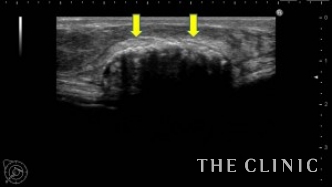

この方は、大胸筋下にシリコンバッグを入れられています。 乳腺と大胸筋の間に4㎝大のしこりがあるのを確認できます。 10年前に注入した脂肪が壊死し、その周りにカルシウムが沈着し石灰化している状態です。

ベイザー波という超音波で石灰化している中のしこりを破壊して除去する場合もありますが、この方法では石灰化している部分は除去できない為、表面から触れる硬さは残ってしまいます。 今回のように広範囲に石灰化している場合は、なるべく傷が目立たない乳輪切開でアプローチしてしこりを全摘出すると、石灰化している外側の殻も除去することが可能です。